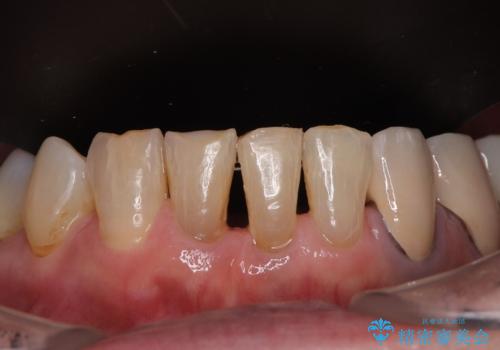

デコボコが強いため、ブリッジや残根となっている部分のスペースを利用して歯列を整え、変色や欠けている歯をオールセラミッククラウンによる補綴治療を行うこととしました。

歯肉移植などによる前歯部の歯肉ライン改善を提案しましたが、口を開けたときにほとんど見えないので気にならないとのことで、特に処置を行うことなく補綴治療を行いました。